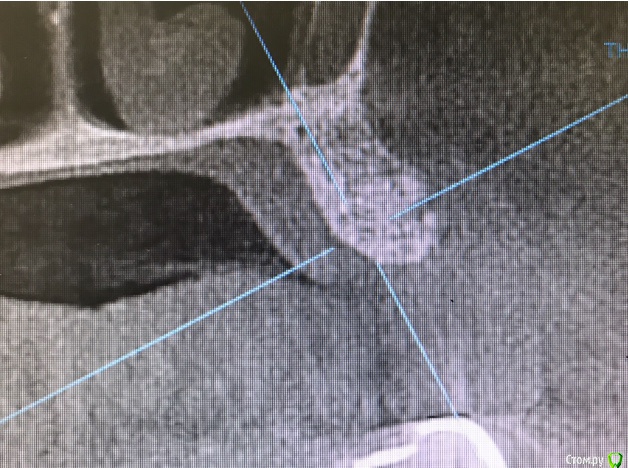

колесников Опубликовано 31 мая, 2019 Автор Поделиться Опубликовано 31 мая, 2019 Ещё случай.Через 3 мес ожидания 4 Ссылка на комментарий

колесников Опубликовано 20 августа, 2019 Автор Поделиться Опубликовано 20 августа, 2019 Очередной случай тоннельной пластики альвеолярного гребня. Был небольшой бонус в виде лунки 26го зуба с дефектом вестибулярной стенки и оас. Лунка консервирована и закрыта «быстрым Ноймайером»,24,25 тоннельный графтинг. Графт тот же,шурос кортикальный без добавок.Контроль и имплантация через 4 мес,через неделю фиксация временной реставрации. Через 2-3 проверим на состоятельность. 4 Ссылка на комментарий